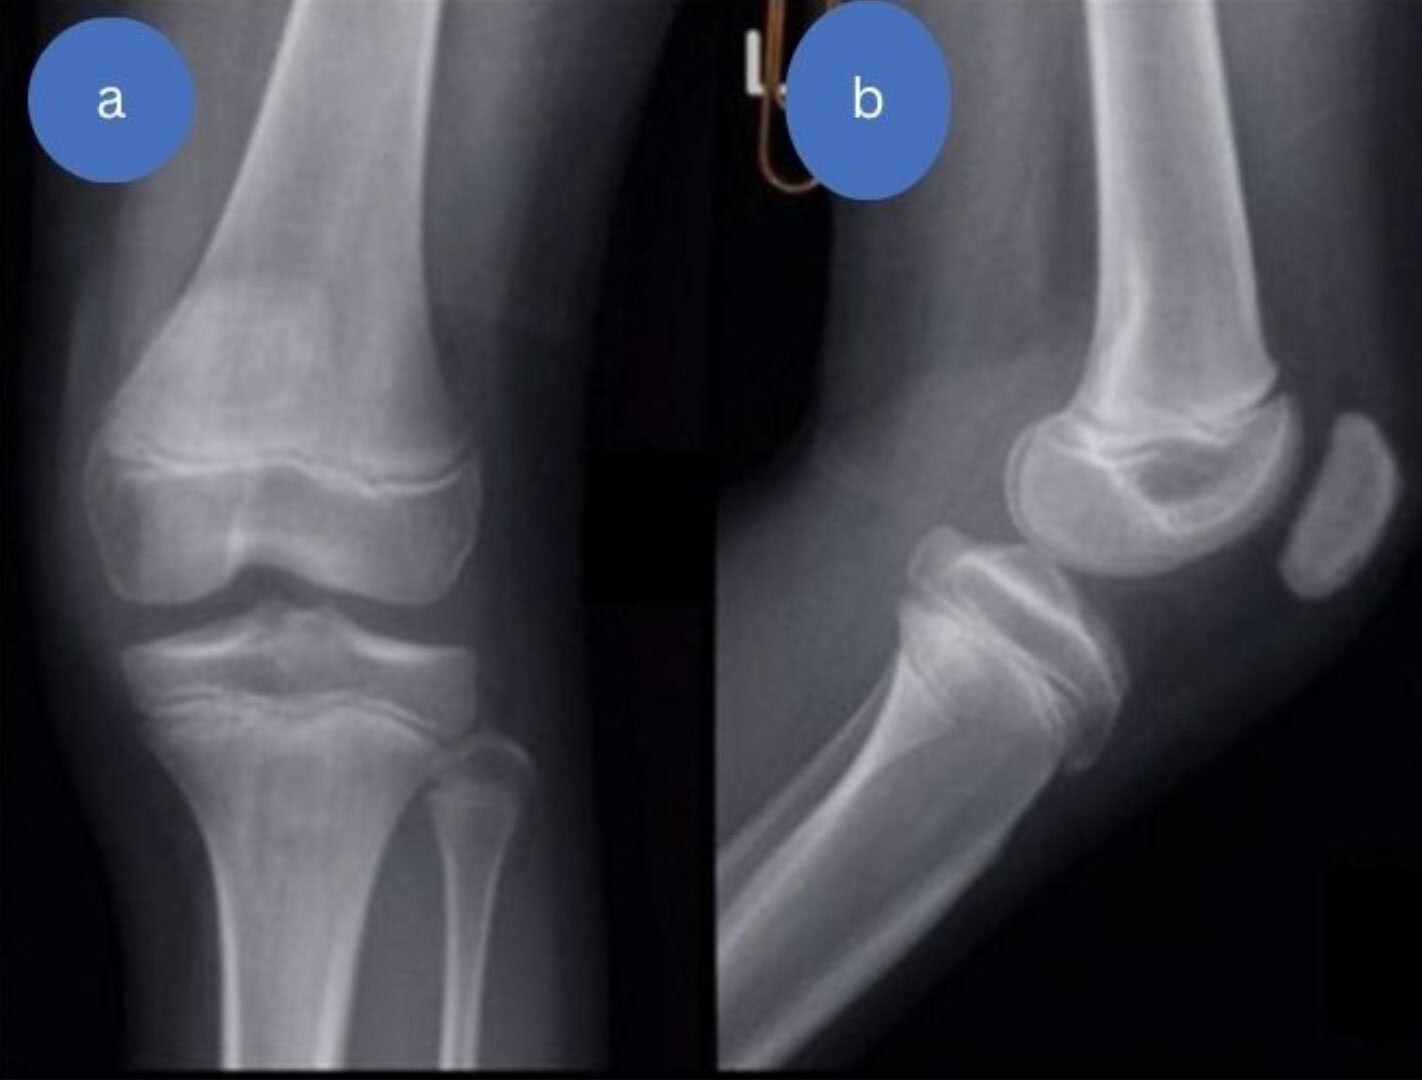

Postoperative radiographs demonstrated satisfactory reduction and fixation (Figures 7,8).